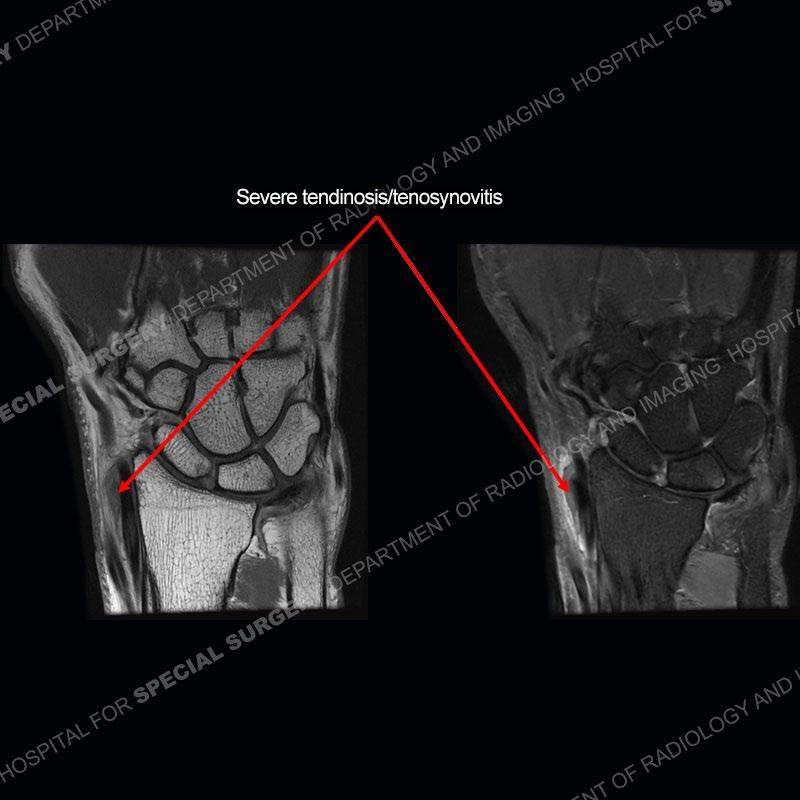

The radiographs in this case are not particularly contributory. The MRI demonstrates tenosynovitis of the first extensor compartment manifest by fluid/synovitis distention of the tendon sheaths. Multiple tendon slips are present of the abductor pollicis longus (APL) and with severe tendinosis seen of one of the tendon slips. Other areas of slightly increased signal and tendinosis are present of the components of the APL. Noted is a somewhat prominent septum separating the more dorsal extensor pollicis brevis (EPB) from the APL.

This case in particular highlights some of the normal variants of the first extensor compartment which can be confusing as well as clinically important. The APL can have multiple tendon slips with the insertion mostly being to the base of the thumb metacarpal but with additional insertions found of the trapezium and occasionally other thenar muscles. With additional tendinosis and partial tearing, this can become particularly confusing.